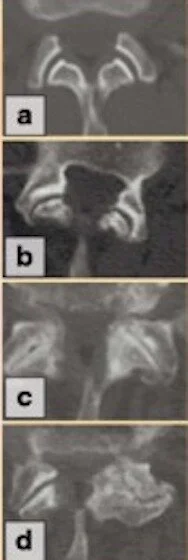

Facet joint degenerative disease from none to severe